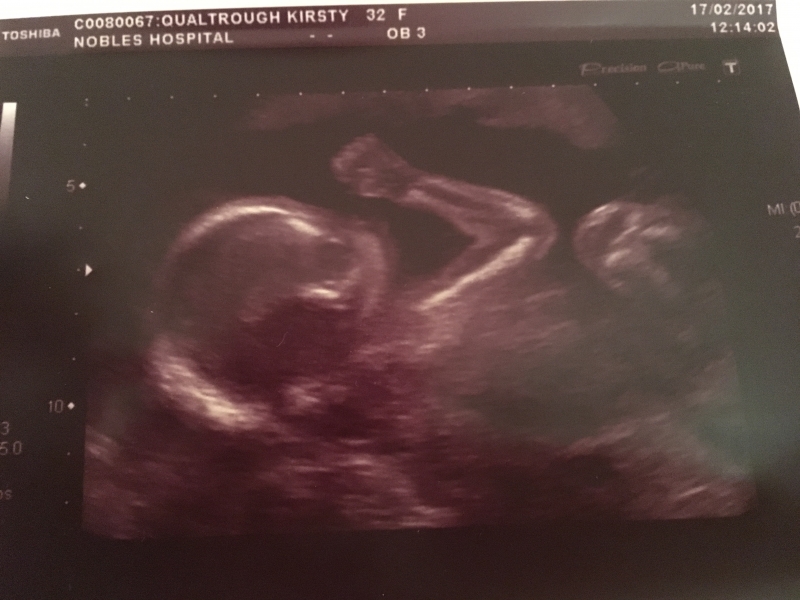

I thought it was time to add a new blog post to bring things up to date as it's been quite busy since the last post in early Feb! I'm now working for Ellan Vannin Chiropractic Clinic as a Chiropractic Assistant (basically receptionist/cleaner), with shifts on a Wed and Thurs morning in Douglas and a Friday afternoon in Ramsey. It's been really good to have a bit of routine and have a role that's really social...only issue is I have to stand for most of the shift (5-6 hours) so not sure how long I'll be able to keep that up! We had our 20 week scan on 17th Feb - it was a relief (and also still a bit scary and completely overwhelming) to see the little one was progressing as it should. Since then I felt my first rumbles and kicks, and now at 23 weeks I'm feeling kicks every day (normally at night after tea), Glenn's also felt them and we've even seen the kicks happening on my tum! Crazy to think what's going on, and that it's a completely natural process that I don't have any control over! So what with the pregnancy progressing it was time for us to seriously think about moving into a bigger place. We decided south would be the best location given that once baby is here I'll be based at home full-time, and as we currently only have the one car it makes sense (and would be nice!) to be near Mum and friends. So we spent a few weekends viewing properties in PE and PSM...some newer builds (Erin Crescent in PE, Creggan Lea in PSM) and also a few older properties (bungalows in Ballamaddrell) but nothing fitted the bill. However, we then heard about a bungalow up Ballakillowey that had been up for rent for ages but had not been lived in and the landlord was willing to negotiate on price. It was so different from anything we'd seen and fitted (most) of our criteria in terms of space, garden, homely. It was a bit neglected having been left for so long however it certainly had more character than anything else we'd seen. So, after negotiating with the agency (Harmony Homes) we secured a year let on 6 Viking Close 🙂 The start of March was busy with packing up and cleaning the flat (wasn't that sad to say goodbye!) and moving south to Colby 🙂 It hasn't quite been plain sailing with the house so far - we've had issues with the heating and washing machine and are still waiting for the hot water pressure to be sorted (it doesn't help that the landlord is based in Norway so nothing happens quickly) however, we already feel settled in and are both really happy we've made the move. Although Glenn's got a bit more of a commute now I think this was the best time to move as it's given us plenty of time to iron out any issues and get settled in ourselves before the little one arrives 🙂 I've already taken advantage of the patio and been sitting out whenever the sun shows itself! This week has mainly been more unpacking and getting bits sorted for the house. Jam, Don and the girls popped up at the weekend..Mum's currently away in Norway on a cruise with her friends Margaret and Tony. After initially being without her luggage as it was 'misplaced' by the coach company she's now enjoying the sights and -2 temperature!) I've now got midwife appointments every month and need to look into aquanatal and pregnancy yoga classes now that I'm starting to get bigger...anything that'll help keep me active, pain-free and potentially help with labour day is top of the list! We're also contemplating booking a 'pre-baby' holiday to have one last relax away from work etc before life changes forever so watch this space for updates! 🙂 Below are a few photos of the last month.